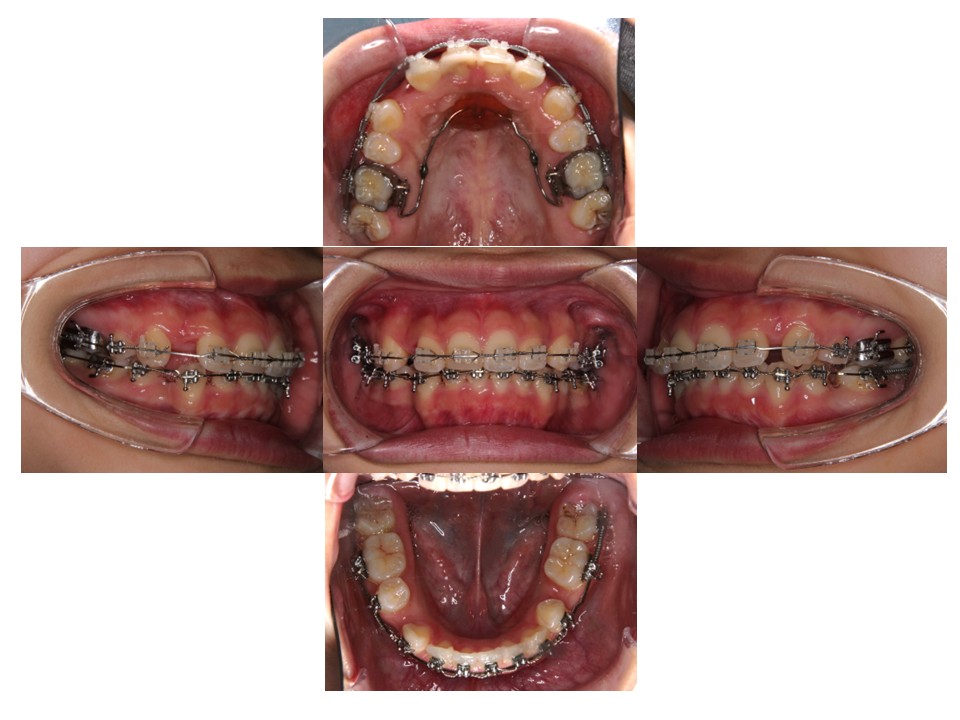

初診時

抜歯を行い、全体的に並べています